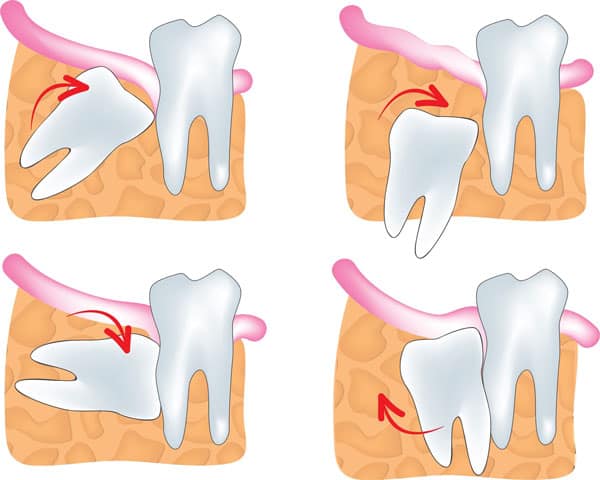

Trên thực tế, việc nhổ răng khôn hàm trên được nhiều người đánh giá dễ dàng hơn việc nhổ răng khôn hàm dưới. Điều này được giải thích dựa vào cấu tạo chung của khuôn hàm, thường thì kích thước hàm dưới nhỏ hơn hàm trên, răng khôn mọc ở dưới sẽ có xu hướng mọc lệch, mọc ngầm nhiều hơn.

Hầu hết răng khôn mọc lệch ở hàm dưới đều có phần chân răng bị biến dạng, cong, vênh nên việc nhổ bỏ sẽ khó khăn hơn, có trường hợp phải cắt chân răng ra làm nhiều phần mới lấy hết chân răng ra được. Đây là lý do mà việc nhổ răng khôn ở hàm dưới sẽ phức tạp hơn và mất nhiều thời gian hơn.